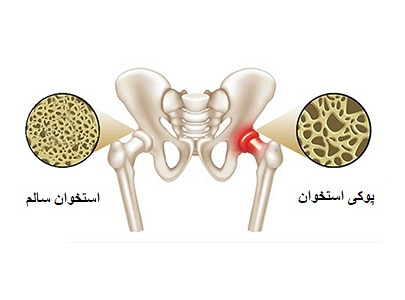

۰۱ آبان ۱۴۰۳هفته پیشگیری از پوکی استخوان

۲۸ مهر ۱۴۰۳